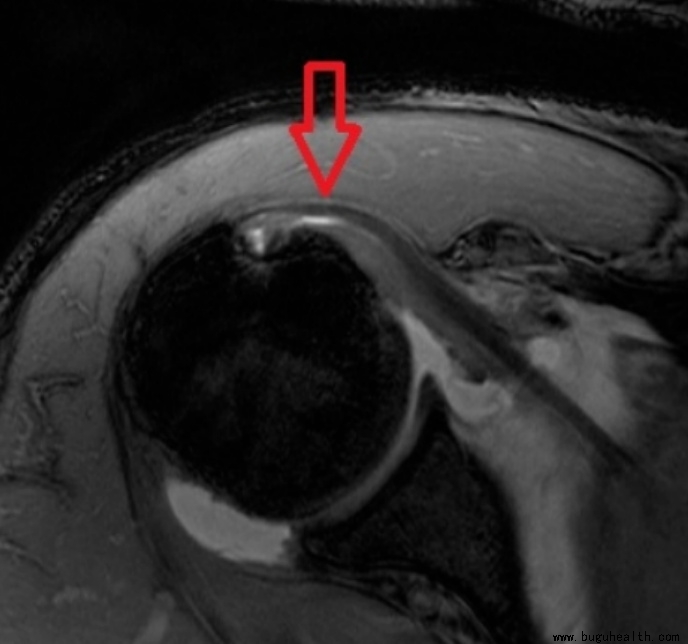

临床上有很多保守治疗的患者,并且都有着不错的效果,避免了手术。例如MRI检查显示仅为肩袖肌群的肌腱仅为部分撕裂的患者,这种情况非常适合保守治疗。而一些患者可能肩袖已经出现了断裂,那么就一定需要手术治疗了。